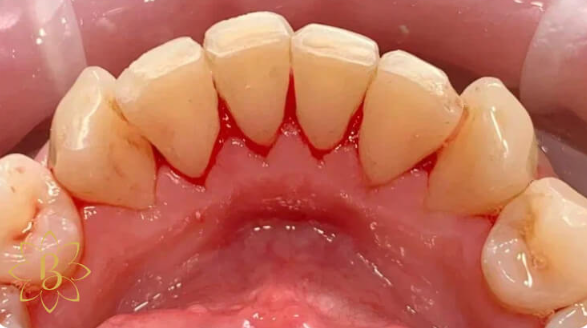

На странице представлено портфолио стоматологий Санкт-Петербурга с работами до и после профессиональной чистки зубов. В нашем портфолио собраны разные клинические случаи: от удаления незначительного налета до снятия массивного поддесневого камня. Здесь вы можете увидеть, как возвращается естественный цвет и внешний вид зубов после процедуры. Изучите результаты до и после чистки зубов, чтобы увидеть реальный эффект и выбрать клинику в Санкт-Петербурге, где профессиональная гигиена поможет вернуть зубам здоровый вид.

Профессиональная гигиена особенно важна при ортодонтическом лечении, ведь в повседневной жизни, дома, очень сложно поддерживать должный уровень гигиены полости рта! Даже если вы используете ирригатор и специальные ёршики! В нашей рубрике «до/после» вы видите то, что может быть с зубами при лечении брекетами, если не проводить своевременную чистку у врача-стоматолога. Марухно Дарья Александровна провела профессиональную чистку в несколько этапов, чтобы вернуть пациентке белизну ее собственных зубов! Брекет-система была поставлена не в нашей клинике, и почему пациентка не обратилась за профессиональной помощью раньше-вопрос) Но в данном случае, главное – итог! Кровоточивость после даже обычной чистки в такой клинической ситуации – естественный результат. Ведь обильный зубной налёт и зубной камень вызывают воспаление дёсен в виде гингивита, а порой даже пародонтита.